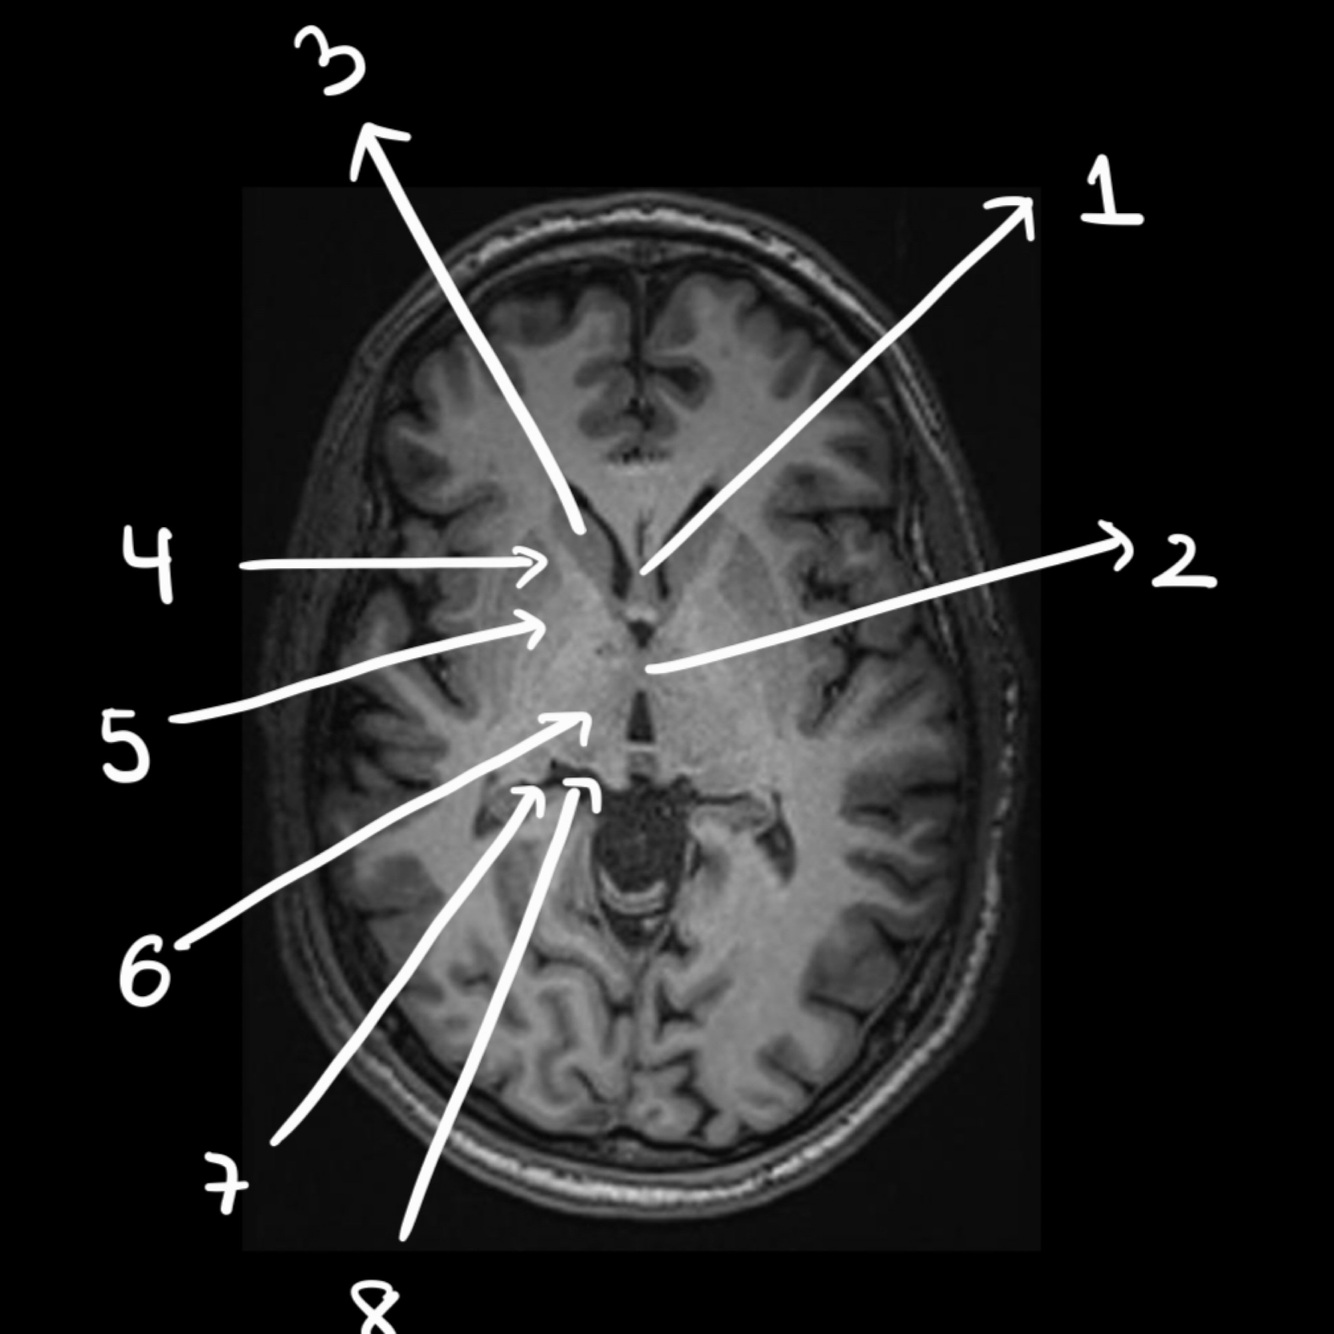

Name the structure

Hypophisis

29

30

4th ventricle